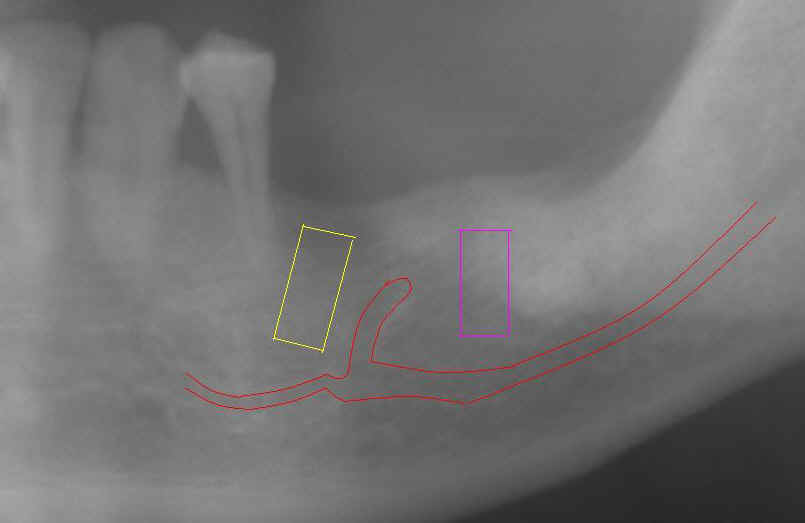

Fig.6 (left) and 7 (right) A PA was

taken immediately before implant placement (Fig.6). There are two radiolucent areas (including one being traced).

The surgeon did not see them or clearly realized that one of them is the

terminal part of the ascending mental nerve. If the sensor had been placed lower, the mental nerve

loop would have been more easily identified (Fig.7). The latter

X-ray was taken before 2nd surgery, which will be discussed below.

The message is that we should adopt paralleling technique (no tilting or distortion) for X-ray and insert the sensor or X-ray film as deep as possible when we place implant around the lower premolars. |